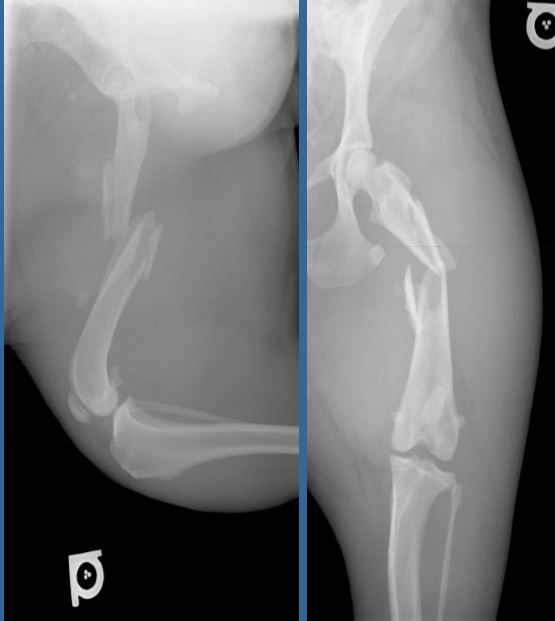

4 month old canine, 10kg

HBC 24 hours ago

Classify and assess fracture, and give repair options

A

Long oblique fracture of the proximal femoral diaphysis

Fx score= 8-10

Repair: IM pin+ cerclage wire, ESF, bone plate